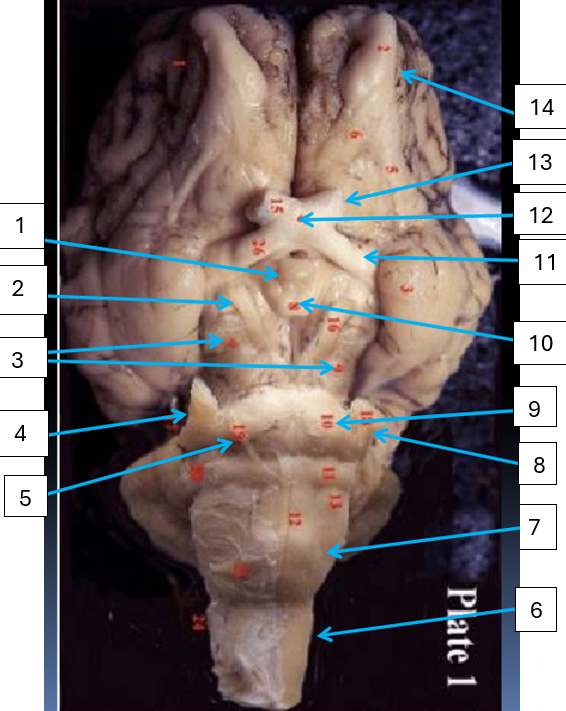

1

pons, connects cerebrum with lower CNS centers

2

abducens nerve, CN6, eye muscle control

3

spinal cord, reflex area

4

medulla oblongata, controls vital autonomic functions like heart rate

5

trigeminal nerve, CN5, motor control of jaw muscles

6

trochlear nerve, CN4, eye muscle control

7

cerebral peduncle, connects cerebrum to pons

8

oculomotor nerve, CN3, eye muscle control

infundibulum, connects hypothalamus to pituitary gland

9

pons, connects brain with lower CNS centers

10

mammillary body, relay station for olfaction

11

optic tract, carries visual information from optic chiasma to visual cortex

12

optic chiasma, area where medial portion of optic nerves cross

13

optic nerve, CN2, vision

14

olfactory bulb, houses synpases of olfactory nerve fibers, CN1, olfaction